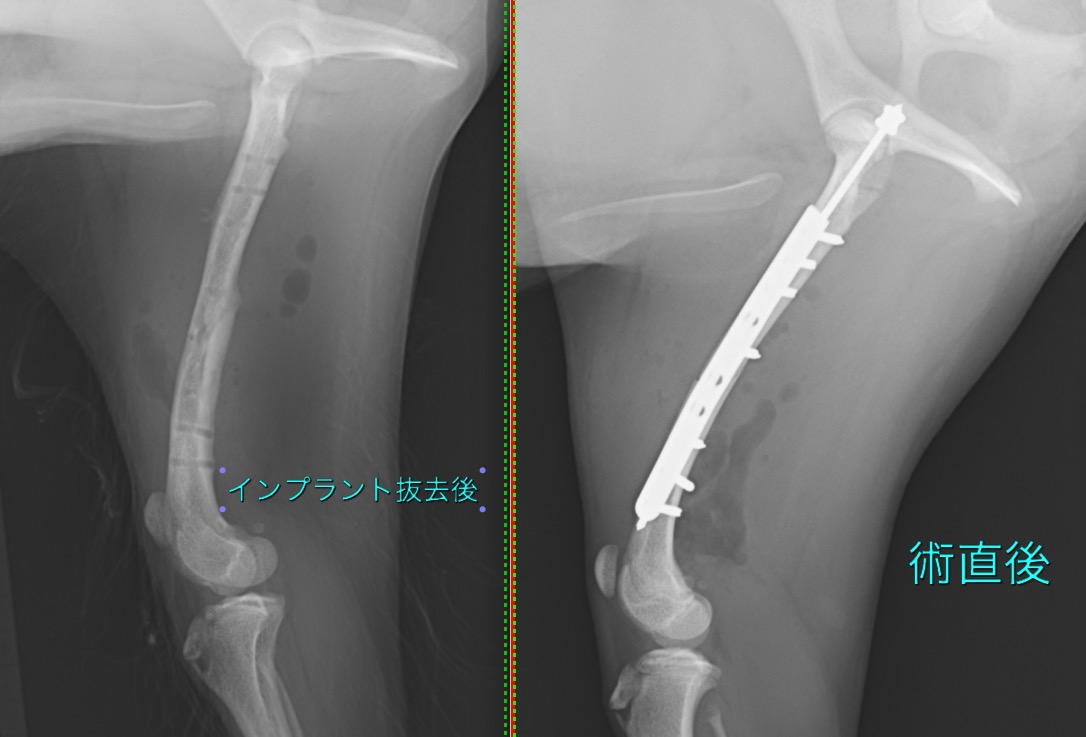

大腿骨骨幹部骨折の小型犬の1例(整形外科、骨折手術、後ろ足、プレート、ピン)

髄内ピンとプレートによる”プレートロッド法”により整復しました。

術後1か月後から段階的にインプラントを間引き、術後2か月半ですべてのインプラントを抜去しました。

術後の経過は良好で、走ったり、ジャンプしたり、問題なく生活できているそうです。